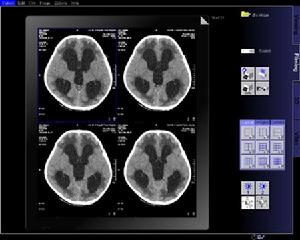

頭部急診平掃cT檢查的操作規範事項應該充分了解cT機器的性能特點,作好機器的定期保養與維護,避免急診cT掃描時機器故障的發生,減少環形偽影的出現為診斷提供正確、直觀、清晰或基本沒有偽影的高質量CT圖像,頭部cT掃描時採用OMI。為基線,頭顱掃描基線過低或下頜過收會掃描出無價值的圖像,或漏掃後顱凹病灶。擺位時掃描基線與瞳間線的平行是保證頭顱cT圖像左右兩側解剖結構對稱的關鍵。它不僅為診斷中左右兩側比較對照提供方便,也為臨床手術測量定位等提供了依據,準確擺位能夠減少重建後處理圖像的時間,縮短了急診病人在掃描床上的滯留時間。嚴格掌握嬰幼兒cT檢查的適應證,掃描時在保證圖像質量的前提下降低毫安量,放大掃描視野。危重症患者在短時間、快速、連續掃描,掃描完畢後採用CT圖像重建作後處理,彌補殘缺圖像,保證CT圖像質量。高齡患者頭頸僵硬可迅速向足側傾斜機架範圍在5b一10b,脊柱後凸或枕骨後傷口縫合等無法仰臥者可採用俯臥位,待掃描結束後進行u—P圖像重建。視窗技術是保證急診顱腦cT圖像質量最後的一個重要技術環節。不同的窗寬窗位對cT圖像顯示有明顯的差異,通過加大窗位並變換不同的視窗技術使血腫與顱骨顯示於不同的灰階,原本不易顯示的小血腫可清楚顯示。3.3CT檢查的注意事項顱腦外傷常伴有其它部位的損傷,搬動病人應採取水平位,避免劇烈體位變化,而加重其它部位的損傷。進行cT掃描前,應先將病人的眼鏡、髮夾等易造成偽影之物品除去,使病人保持安靜不動。因嚴重顱腦外傷及腦血管意外病人多伴有不自主運動及煩躁不安,cT掃描過程中如掃描部位有移動,會產生偽影使影像失真,cT圖像質量下降;因觀察困難,導致假陽性或假陰性之診斷口j。密切注視病人呼吸道的通暢。如病人頭部過度屈曲,呼吸道部位阻塞,可發生憋氣,已用足量鎮靜藥的病人可出現不安靜,反而使運動增加。因此不要過分要求病人低頭,使聽眥線呈零度。布帶固定制動為最簡單方法之一。病人仰臥位,頭部枕於掃描頭架上,用頭部固定布帶固定患者前額及下額部於掃描架上,此方法適用於淺昏迷或半昏迷煩躁不安病人。